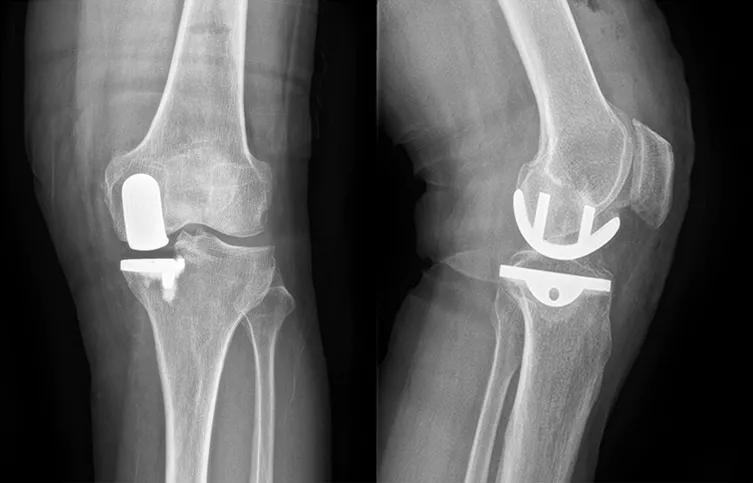

(1)70岁女性患者,以左膝关节疼痛5年、加重1年为主诉入院,入院查体左下肢内翻畸形11°,膝关节内侧间隙压痛阳性,外侧无压痛,髌骨研磨试验阴性,抽屉试验阴性,ROM 5°~120°,诊断左膝关节前内侧骨关节炎,行左膝关节内侧固定平台单髁置换术。术后给予预防感染、消肿止痛及抗凝治疗,术后24h康复师指导助行器辅助下床活动,术后1个月膝关节HSS评分由63分升至85分,KSS评分由49分升至80分,内侧疼痛消失,患者恢复满意。手术前后影像学资料见图1~2。

图1术前 X线片示内侧间隙呈骨对骨改变

图2术后 X线片示假体位置良好,大小合适